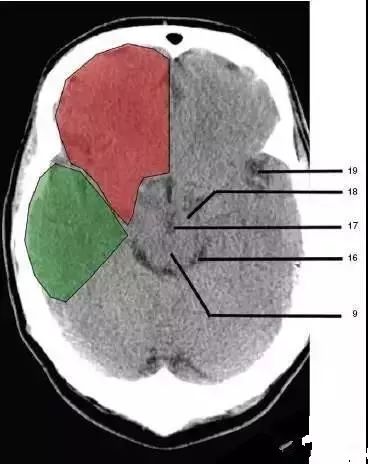

16、环池(Ambient cistern)

17、角间池 (Interpeduncular cistern)

18、大脑角(Cerebral peduncle)

19、侧裂池(Sylvian fissure):绿色部分为颞叶(Temporal Lobe),浅红色部分为额叶(Frontal Lobe)